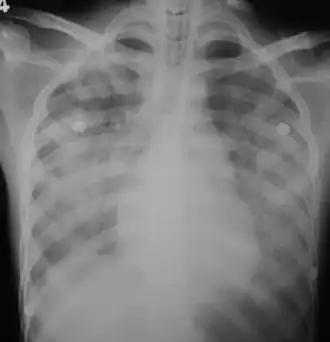

In those who have lung involvement, a chest X-ray may demonstrate diffuse alveolar opacities.[13]